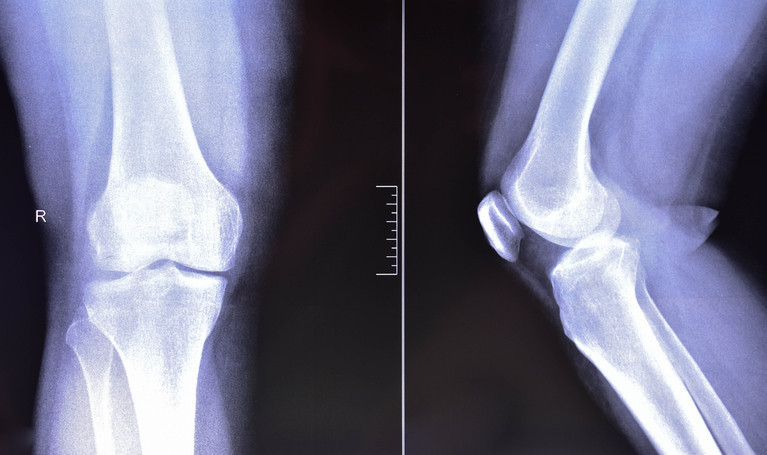

Doktorlar, motosiklet kazalarında ayak bileği, diz ve kalça çevresinde ciddi kırıklarla sıkça karşılaştıklarını belirtiyor.

Aşırı hız nedeniyle hastalar ciddi travmalarla geliyor. Çoğu genç olan sürücülerde ayak bileği, diz ve kalça çevresinde parçalı ve eklem içi kırıklarla karşılaşılıyor.

Bazı kırıklar uzun vadeli sakatlık riski taşıyor. Kalça yuvasının kırılıp femur başının yuvadan çıktığı asetabulum kırıklarıyla sık karşılaşıyoruz. Bu kırıkların tedavisi oldukça zor.

Eklem içi kırıklarda ilerleyen yıllarda hareket kısıtlılığı ve kalıcı sakatlıklar görülebiliyor. Genç yaşta yaşanan bu kazalar, hastalarımızın hem iş hem de sosyal hayatını ciddi şekilde etkiliyor.